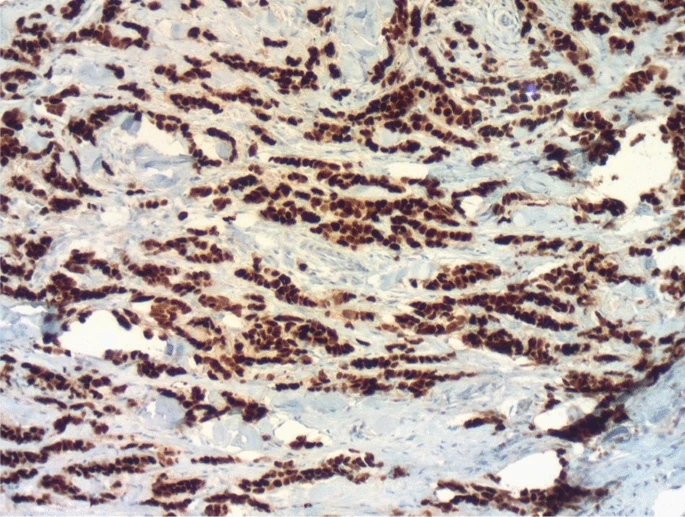

Five of the 28 recovered nodules were metastatic lymph nodes, with two exhibiting extra capsular expansion. The remaining 14 nodules were classified as TDs. They were tumor clusters that existed independently, with no lymphocytic peripheral rim or remnant vascular or neural walls. The tumor staged as ypT1aN2aM0. The patient continued to undergo hormone therapy along with trastuzumab. The follow-up revealed no issues. The patient remains in good clinical condition. There is no evidence of a recurrence.

In this case, we found 14 TDs and five lymph node metastases in the axillary area of a woman who had a mastectomy and axillary dissection for a high-grade luminal B HER2-positive invasive breast cancer. In this scenario, TDs were identified using the same criteria as for colorectal cancer (CRC). These criteria include the absence of a lymphocytic peripheral rim and capsule, as well as the lack of a remnant vascular wall or neural tissue within the tumor cluster. Although TDs were not included in the N classification, their presence and number were clearly reported in our final pathology report.